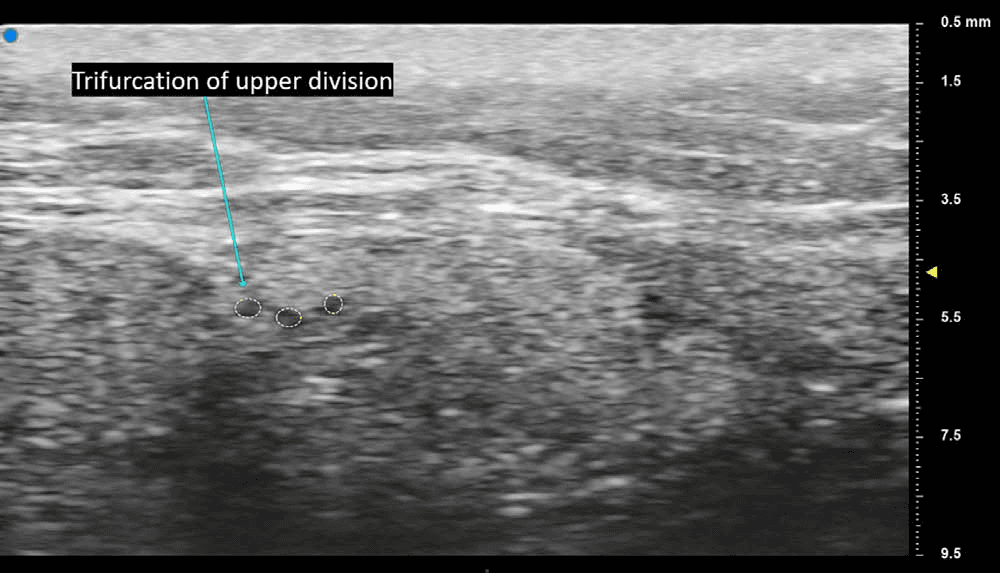

안면마비 - 안면신경 상분지의 삼분지 분기점을 축상면 초음파로 시각화한 영상입니다. 먼저 축상면 스캔으로 신경 구조를 확인한 후, 신경을 영상 중앙에 유지하 Figure 3. 안면신경 상분지의 삼분지 분기점을 축상면 초음파로 시각화한 영상입니다. 먼저 축상면 스캔으로 신경 구조를 확인한 후, 신경을 영상 중앙에 유지하면서 조심스럽게 프로브를 회전시켜 종축면으로 전환하는 동적 초음파 검사법이 적용되었습니다. 이는 복잡한 안면신경 분지의 해부학적 변이를 수술 중 실시간으로 파악할 수 있는 유용한 기법임을 보여줍니다.

안면신경의 관골지(zygomatic branch)와 협부지(buccal branch)를 축상면 초음파로 명확하게 구분하여 관찰할 수 있었으며, 각 분지가 서로 다른 층에서 주행하는 모습이 실시간으로 구별되어 나타났습니다.